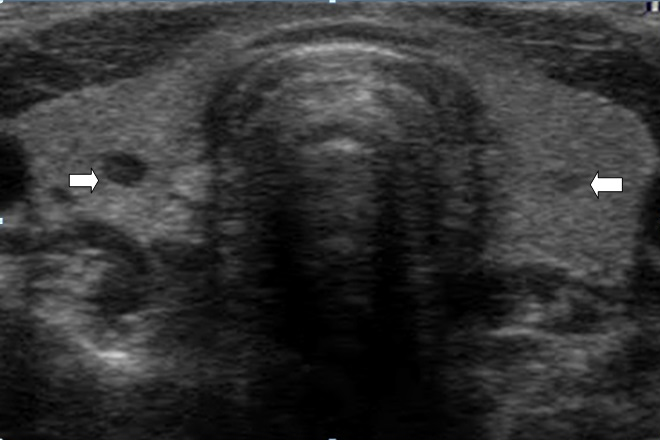

Se consideró como tejido tiroideo normal aquel con una ecogenicidad homogénea mayor que la de los músculos adyacentes. Se definieron los nódulos como imágenes bien delimitadas dentro del parénquima tiroideo, pudiendo ser únicos o múltiples. Se clasificaron las características de los nódulos en:

1. Anechoico.

2. Hipoecoico.

3. Isoecoico.

4. Hiperecoico.

5. Patrón Mixto.